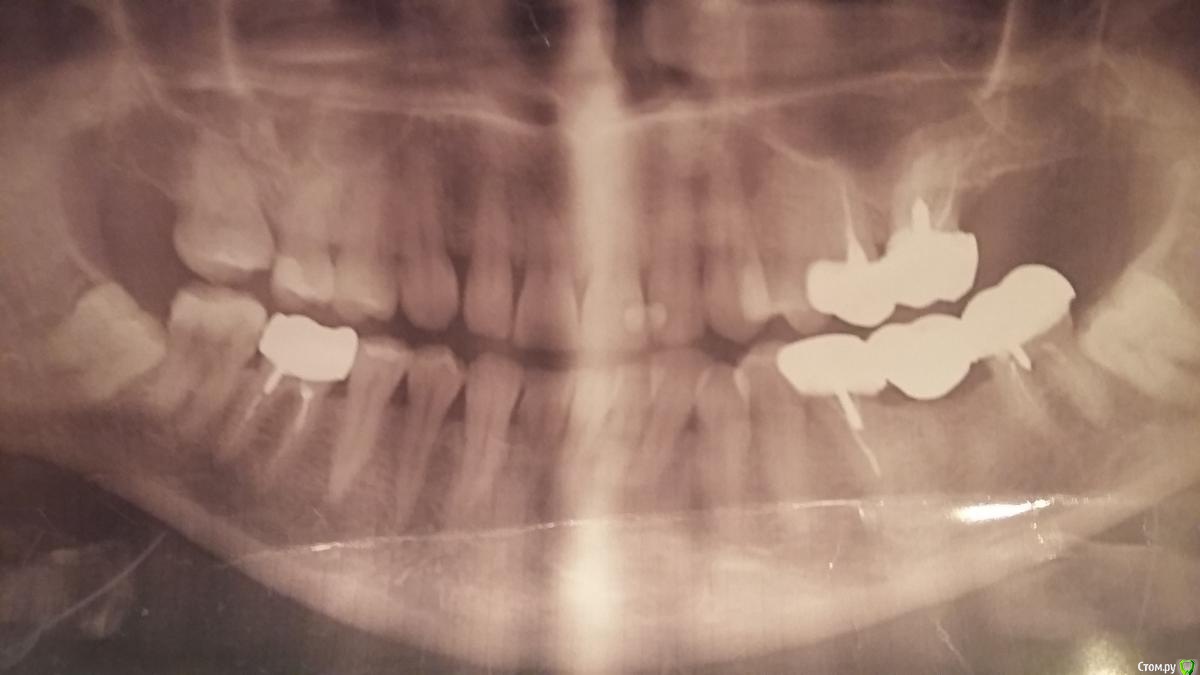

Алламур Опубликовано 29 марта, 2017 Поделиться Опубликовано 29 марта, 2017 http://s019.radikal.ru/i612/1703/58/8958c4105a36.jpg Ситуация такая. Хочу снять десятилетние коронки- так как запах и нитка рвется и т.д.Предлагают- удалить последние зубы и поставить импланты. Вопросы:1- можно ли сохранить последние зубы с правой стороны снизу и сверху?2 обязательно ли удалять поддесновой (мудрость под десной) зуб справа снизу ?3 подойдет ли мне одномоментная имплантация?Дорого но очень мило сердцу4 Нужно ли делать наращивание и лифтинг? (ничего не понимаю- слова доктора)5 Пока не имею фин возможности могу ли установить на треснувший верхний последний зуб розового! цвета отдельную коронку на "авось еще простоит годочков пять- а я подкоплю". Или не стоит тратить 10 тыс? http://s019.radikal.ru/i612/1703/58/8958c4105a36t.jpg Ссылка на комментарий

red_butler Опубликовано 30 марта, 2017 Поделиться Опубликовано 30 марта, 2017 1- можно ли сохранить последние зубы с правой стороны снизу и сверху? Вы стороны не путаете? 2 обязательно ли удалять поддесновой (мудрость под десной) зуб справа снизу ? желательно удалить оба 3 подойдет ли мне одномоментная имплантация?Дорого но очень мило сердцу на нижней челюсти, скорее всего это возможно 4 Нужно ли делать наращивание и лифтинг? (ничего не понимаю- слова доктора) да Ссылка на комментарий

red_butler Опубликовано 30 марта, 2017 Поделиться Опубликовано 30 марта, 2017 А давно сделан этот снимок? По нему однозначных показаний к удалению не увидел Ссылка на комментарий

Алламур Опубликовано 30 марта, 2017 Автор Поделиться Опубликовано 30 марта, 2017 Снимок сделан неделю назад. Врач сказал с правой стороны(если смотреть на снимок) или с левой у меня во рту- последние зубы и свекрху и снизу надо удалять. Последний сверху треснул пополам и "розовый"- такие зубы она не перелечивает ) Может можно поставить не перелечивая коронку или не простоит долго? Ссылка на комментарий

St. Опубликовано 30 марта, 2017 Поделиться Опубликовано 30 марта, 2017 могу ли установить на треснувший верхний последний зуб розового! цвета отдельную коронку на "авось еще простоит годочков пять- а я подкоплю". Или не стоит тратить 10 тыс? Если есть трещина, то зуб однозначно не жилец. И 5 лет он точно не прослужит. Не стоит тратить денег, имхо. Единственный вариант оттянуть решение - пока не трогать совсем, т.е. не снимать верхние коронки. Ссылка на комментарий